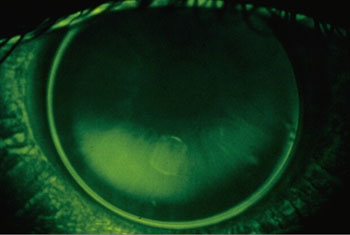

| Fluobild, Grad -1: |

| Wird die Kontaktlinse ca. 1/10 steiler

angepasst als der zentrale flache Hornhautradius, kommt es zu einer

leichten Steilan-passung.

Das Zentrum der KL hebt sich etwas über die Hornhaut hinaus.

Es ensteht ein kleiner heller Fluosee, die Peripherie der KL liegt

auf der Hornhaut auf.

Diese Art von Anpassung kann toleriert werden, zumal man in einigen

Fällen durch eine leichte Steilanpassung besseren Zentrierungseigenschaften

der Linse erreicht. |